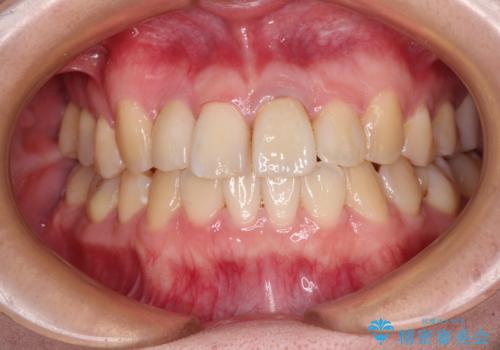

虫歯治療ついでに歯並びの後戻りを改善 インビザラインによる矯正治療

- 奥歯が痛いとのことで来院された患者様です。

上顎親知らず周辺の炎症と、神経組織の失活した歯の炎症による痛みが認められたため、親知らずの抜歯と根管治療を行いました。

根管治療を行った歯はクラウンによる補綴治療が必要となりますが、高校生の頃に行った矯正治療の後戻りも気になるとのことで、補綴治療を行う前に矯正治療を行うこととしました。

後戻りは軽度であり、インビザラインにて歯列を整え、その後にオールセラミッククラウンにて補綴治療を行うこととしました。

ご家庭やお仕事の都合で通院が途絶えた時期があり、治療は長期間となりましたが、無事に終えることができました。